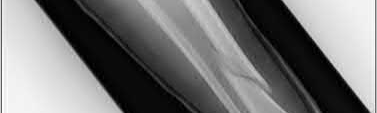

A 38-year-old male suffers the injury shown in Figure A. During operative fixation, free osteoarticular fragments are encountered and reconstruction of these pieces is attempted. Postoperatively, which of the following will have the most beneficial effect on the healing potential of the surviving chondrocytes within these reconstructed articular segments?

Figure A demonstrates a comminuted tibial plateau fracture with significant intra-articular involvement. Basic science evidence has demonstrated that post-operative gentle compressive loading may have a positive impact on articular cartilage healing; however, excessive shear loading may be detrimental.

Irrgang et al provide guidelines for rehabilitation following surgical management of articular cartilage lesions of the knee. They state that after articular cartilage repair, exercises to enhance muscle function must be done in a manner which minimizes shear loading of the joint surfaces in the area of the lesion. The authors also discuss the benefits of gentle compressive loading and motion of the joint, and its positive effects on chondrocyte nutrition.

Furthermore, they recommend a period of protected weight bearing as often being necessary, and that this should be followed by progressive loading of the joint.